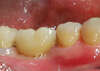

POSE D' IMPLANT DENTAIRE MOLAIRE DU BAS